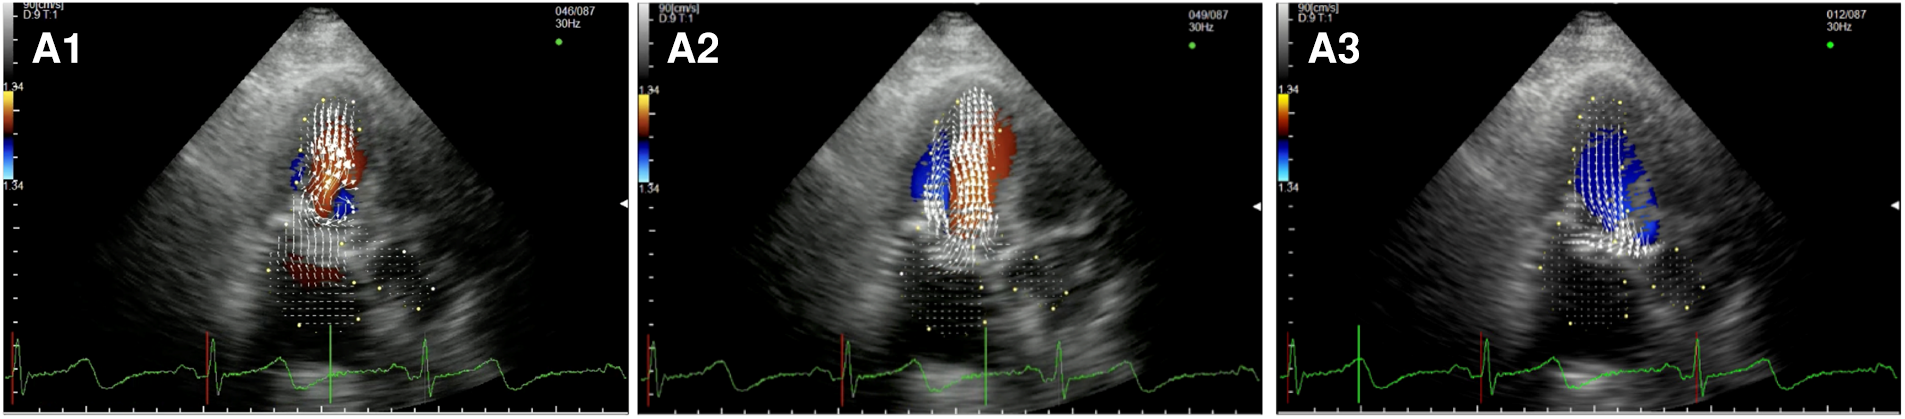

In the healthy controls (Figure 1, panel A1,A2,A3, Supplementary Video S1), blood enters the LV cavity through the MV smoothly, creating two vortices that move in opposite directions, a main clockwise vortex beneath the AML and a smaller counterclockwise vortex beneath the PML. While the posterior vortex dissipates quickly, the anterior vortex keeps getting bigger during diastole moving downstream and pushing the blood flow towards the posterior wall of the LV and then redirecting the flow towards the LVOT during systole. In systole, hemodynamic forces are directed mainly along the left ventricle longitudinal axis, from the apex to the LVOT, without significant vortices (i.e., vortices that persist for at least two consecutive frames).

Figure 1

Apical long-axis view. Intracardiac flow vectors in early diastole (A1–C1) and late diastole (A2–C2) for control patient, patient with DMR and patient with FMR respectively; intracardiac flow vectors in mid-systole for control patient (A3), patient with DMR (B3) and patient with FMR (C3).

In patients with DMR (Figure 1, panel B1,B2,B3, Supplementary Video S2),the diastolic flow pattern composed ofthe two LV vortices is preserved. However, during late diastole and early systole, the anterior vortex does not direct the flow toward the LVOT because the hemodynamic forces are directed from the apex to both the LVOT and the left atrium due to the posterior leaflet prolapse, leading to the formation of multiple vortices proximal to the MV (mainly with a clockwise rotation). In FMR (Figure 1 panel C1,C2,C3, Supplementary Video S3), we observed only one clockwise vortex distal to the AML during early filling. In systole, because of PML tethering causing MV malcoaptation, hemodynamic forces are directed from the apex both to the LVOT and to the left atrium leading to the formation of a counterclockwise vortex proximal to the MV.